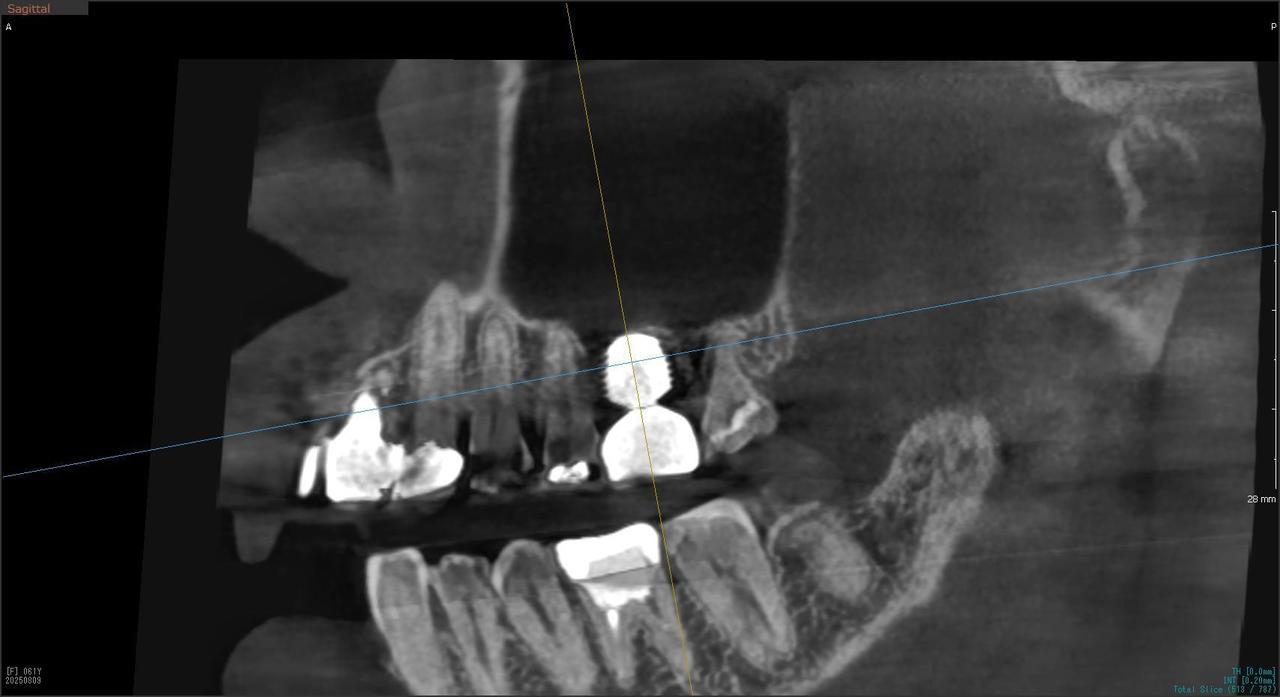

5.右上6番の歯根が破折したに大きな骨欠損を生じたケースに対して、通常なら、大幅な増骨手術(GBRとサイナスリフト)が必要で、最低1年は、かかるケースを、骨補填材なしで、インプラント埋入後、2.5か月で治療を終えたケース

Before

枚方市のインプラントの症例

H・M様 女性 60代

症状としては、左上6番の歯根が歯根が破折したために、炎症が起き、上顎洞底までの及ぶ大きな骨欠損がおきていた、

治療法としては、動揺がひどくなってきて、炎症の症状もあったため、抜歯を希望。抜歯後にインプラント治療を希望したために、CTを撮影したところ、かなりの骨欠損が生じていた。インプラントは不可能か大幅な増骨手術が必要なるようなケースであったが、ご自分の骨が少し残っていた部分にエクストラワイドインプラントで固定をとることと、グラフトレスサイナスリフトを併用する計画を立て、インプラント埋入術を施行。2か月後、インプラントがデータ測定上安定したために、光学印象で印象を行い、2か月半後に上部としてジルコニアクラウンを装着して治療を終えています。

治療結果として、大幅な骨欠損があったが、2か月半という短時間で治療を終えることができた。通常のサイナスリフト等の大幅な増骨手術を行った場合、患者様に、肉体的、金銭的、時間的な負担をかけることになったが、グラフトレスサイナスリフトとエクストラワイドインプラントを使用することにより、そのことを避けることができた。

治療の期間・回数:治療回数インプラント埋入後6回

治療の価格:363000円(税込)

治療費の内訳:インプラント基本料(フィックスチャー(メガジェンインプラントANYONE) 及び手術費用、投薬費用、レントゲン費用、インプラント上部費用(アバットメントおよびジルコニアクラウンの費用用)330000円(税込み)左上6グラフトレスサイナスリフト費用 33000円(税込)

治療のリスクや副作用:手術後に、痛みや腫れ、出血、合併症などを引き起こす可能性があります。噛む感覚がご自身の歯と異なる場合があります。見た目がご自身の歯と異なる場合があります。手術後にメインテナンスを継続しないと、インプラントが抜け落ちる可能性があります。